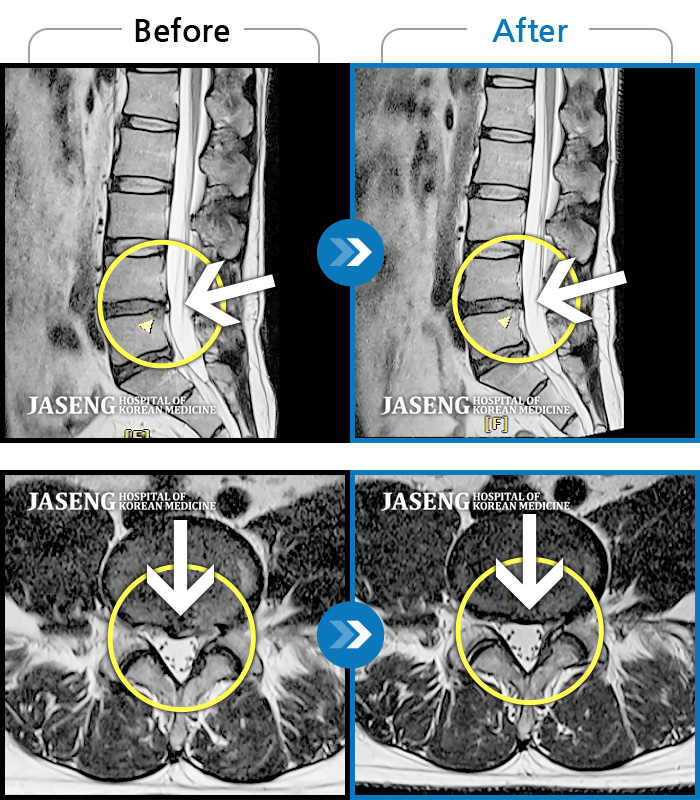

허리디스크

광주 · 장영우 원장

양측 허리부터 골반 묵직한 통증, 좌측 다리 외측까지 이어지는 당기는 통증으로 내원하셨습니다.

촬영시기

2503.04.01 ~ 2509.11.01

2025.09.22